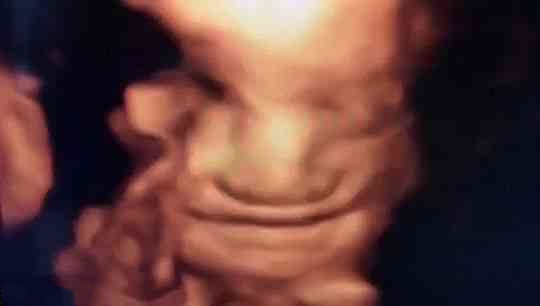

苗苗怀孕5个半月的时候去做四维彩超,她一直注视着大屏幕上宝宝的一举一动。忽然,她看到胎宝宝咧嘴笑了,这给她大大的惊喜,同时,她又很惊讶,宝宝在肚子里也会笑?常听说宝宝出生后还不会笑呢?

医生说:很正常,我们做四维彩超经常看到有宝宝笑。苗苗才知道自己是少见多怪了,而医生见的多了觉得稀松平常。

其实,关于胎宝宝在肚子里微笑,类似的报道并不少见,很多妈妈反馈过做四维时看到宝宝笑的样子,国外媒体也经常报道类似的新闻。

2018年,英国《每日邮报》报道,一对夫妇在做四维彩超时发现宝宝咧嘴微笑,让父母感到喜出望外。

从这里看出,在做四维彩超的时候很容易捕捉到胎儿的微笑,这时不要觉得奇怪,这是胎儿正常的生理反应。